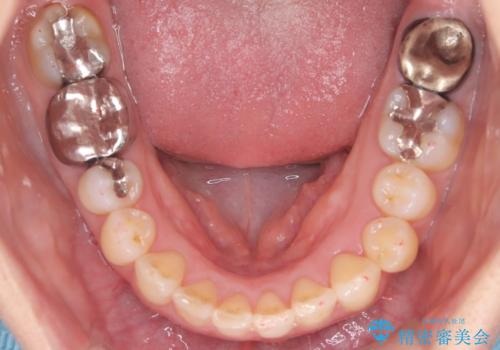

【インビザライン】重度叢生をなおしたい

- 全体的に歯並びをなおしたいことを主訴に来院されました。

上顎前歯が舌側傾斜していたため少し拡大を行いながら非抜歯で治療を行っています。

マウスピースをしっかり使用していただいたので、きれいな歯並びになりました。